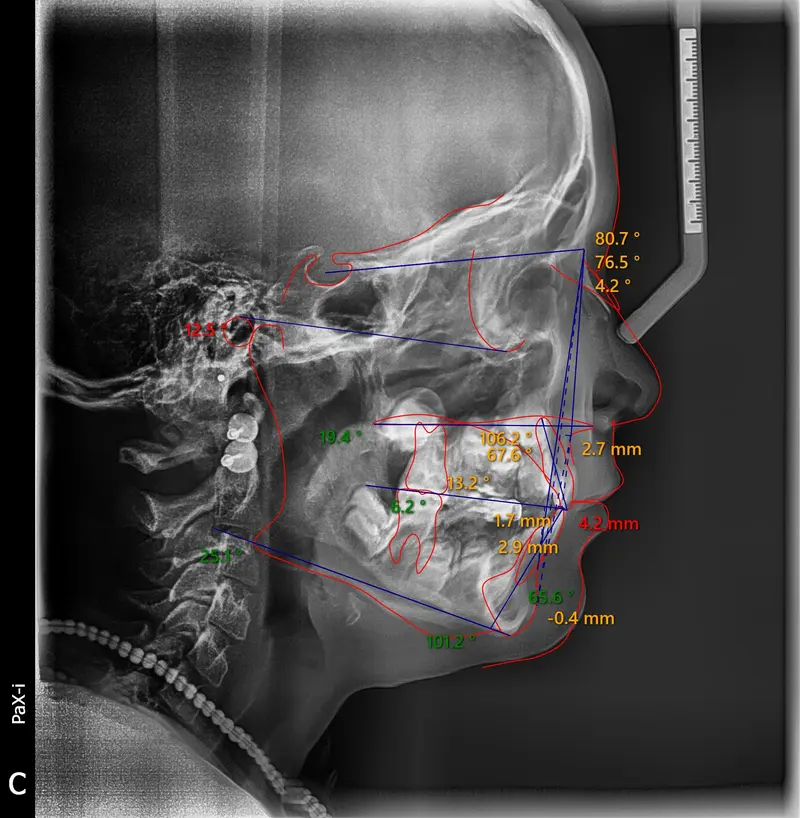

The Diagnosis

Bimaxillary protrusion (teeth flaring forward) causing lip incompetence. The patient struggled to close his lips comfortably, straining the chin muscle (mentalis).

The Engineering

A strategic extraction plan (4 premolars) allowed us to retract the front teeth. Note the dramatic improvement in chin projection and facial balance. The extractions did not flatten the face; they harmonized it.